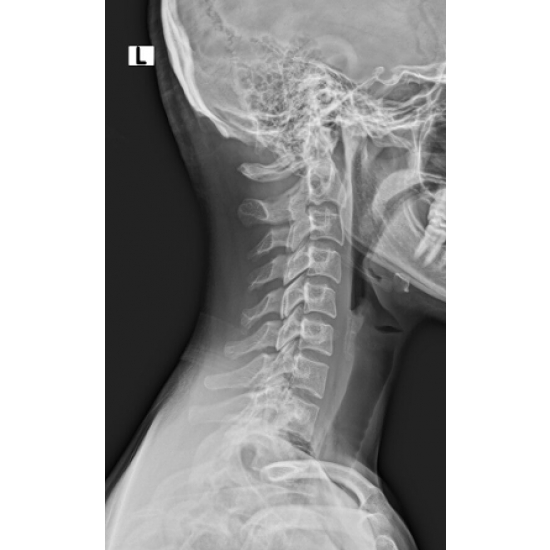

XR 4+ view cervical spine: Normal vertebral body and disc height. No acute osseous abnormality. Case Photo #1 , Case Photo #2 , Case Photo #3 , Case Photo #4